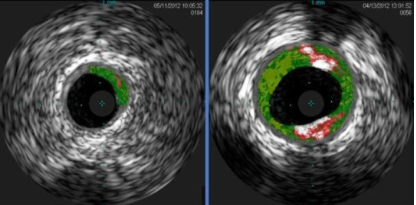

Allergen in Red Meat Linked To Heart Disease

A team of researchers says it has linked sensitivity to an allergen in red meat to the buildup of plaque in the arteries of the heart. While high saturated fat levels in red meat have long been known to contribute to heart disease for people in general, the new finding suggests that a subgroup of […]